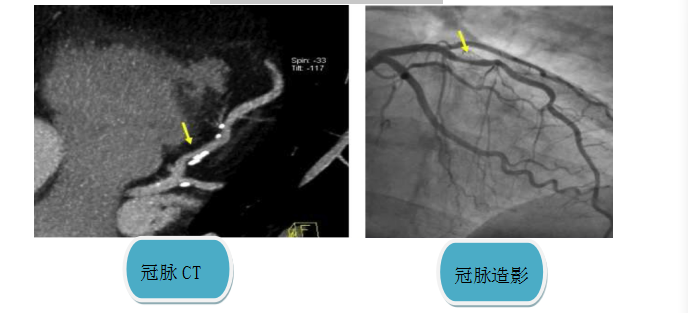

下图箭头所示:冠脉存在钙化及狭窄